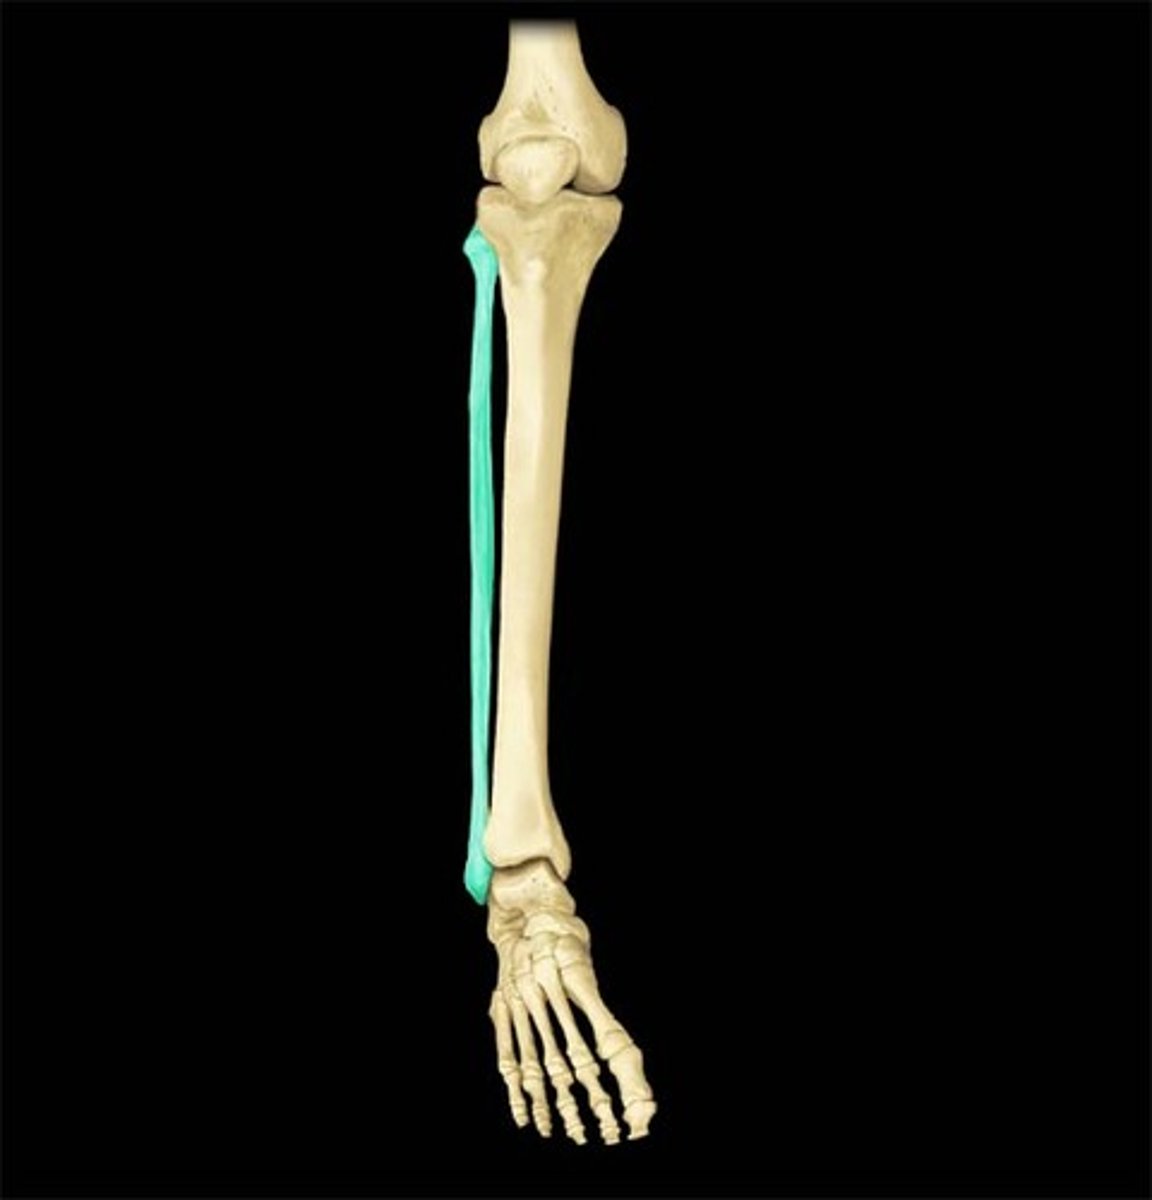

fibula

1

tibia

2